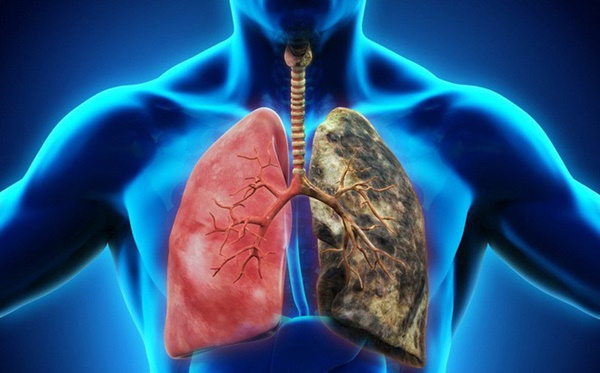

Là hình thức ung thư phổi phổ biến với phụ nữ, đặc biệt được phát hiện ở những người không hút thuốc, dưới 45 tuổi và hầu hết là người châu Á. Kiểu khác của loại ung thư phổi này là ung thư phổi phế nang được tìm thấy ở những phụ nữ trẻ không hút thuốc. Hiện nay ung thư phổi biểu mô tuyến vẫn ngày một tăng khi ung thư phổi biểu mô tế bào có dấu hiệu giảm.

Nguyên nhân các bệnh ung thư phổi nói chung một phần đều do hút thuốc. Cũng có rất nhiều trường hợp không hút thuốc là do tiếp xúc radon bên trong nhà. Ung thư phổi biểu mô tuyến là sự kết hợp nhiều yếu tố khác nhau.